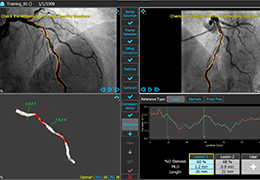

ANYTHINK 经导管主动脉瓣膜置换术分析系统